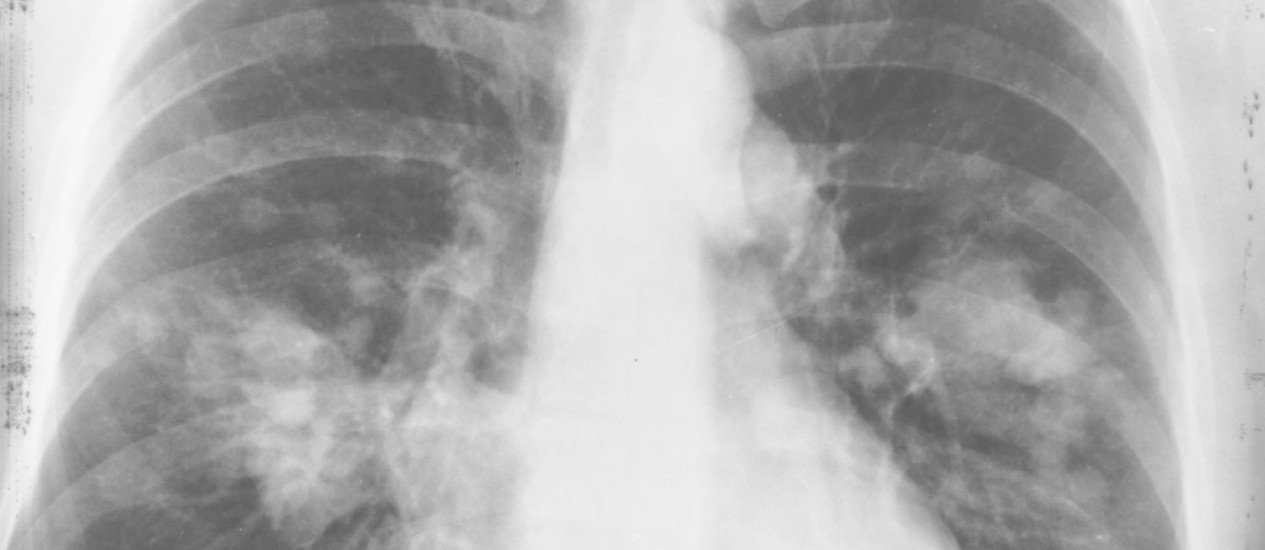

CHICAGO - O avanço das pesquisas sobre imunoterapia no combate ao câncer — que faz com que o próprio organismo do paciente combata as células cancerosas — nos últimos dois anos está deixando para trás a era em que a quimioterapia era a única forma de tratar tumores de pulmão em estágio avançado. Exemplo disso é um ensaio clínico apresentado há dez dias nos EUA por um pesquisador brasileiro, que comparou imunoterapia com a substância pembrolizumabe e quimioterapia padrão em pacientes com câncer de pulmão avançado ou metastático. Esse é o tipo de câncer mais letal. O Instituto Nacional do Câncer (Inca) prevê 30 mil novos casos no Brasil este ano. O estudo mostrou que a imunoterapia é capaz de dar maior sobrevida com menos efeitos colaterais aos pacientes.

A imunoterapia agora também pode ser usada em combinação com o tratamento convencional, a quimioterapia, no Brasil. A Agência Nacional de Vigilância Sanitária (Anvisa) autorizou, ontem, a inclusão do uso combinado do pembrolizumabe com quimioterapia como primeira opção de tratamento de câncer de pulmão avançado de não pequenas células, o tipo mais comum, que responde por 85% dos casos.